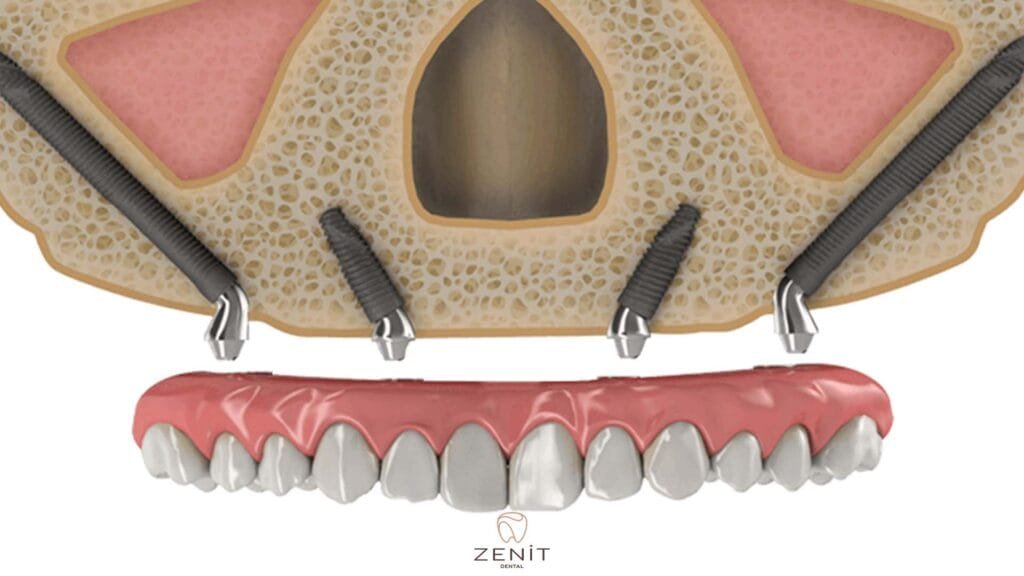

Zygoma implants offer an excellent alternative for patients with inadequate jawbone and provide a revolutionary treatment in the facial area. These special implants, unlike traditional implants, are placed in the zygomatic (zygoma) bone instead of the upper jaw bone. Since the zygomatic bone has a denser and stronger structure than the jawbone, zygoma implants can be safely placed in this area. Thanks to zygoma implants, even patients with advanced bone loss can achieve aesthetically and functionally satisfactory results.

Zygoma implants placed in the cheekbone, unlike other dental implants, are placed not in the jawbone, but in the area called zygomatic bone, which is located in the middle of the face and has a very solid structure. The zygomatic bone has a denser structure than other bones and bone loss usually does not occur. Thanks to this feature, zygoma implants offer a safe and effective solution to patients with jaw bone deficiency.

- Implant Placement: Zygoma implants are placed in the cheekbone instead of the upper jawbone. The surgeon works with high precision when placing the implants, because reaching the zygomatic area and placing the implants in the correct position requires great care.